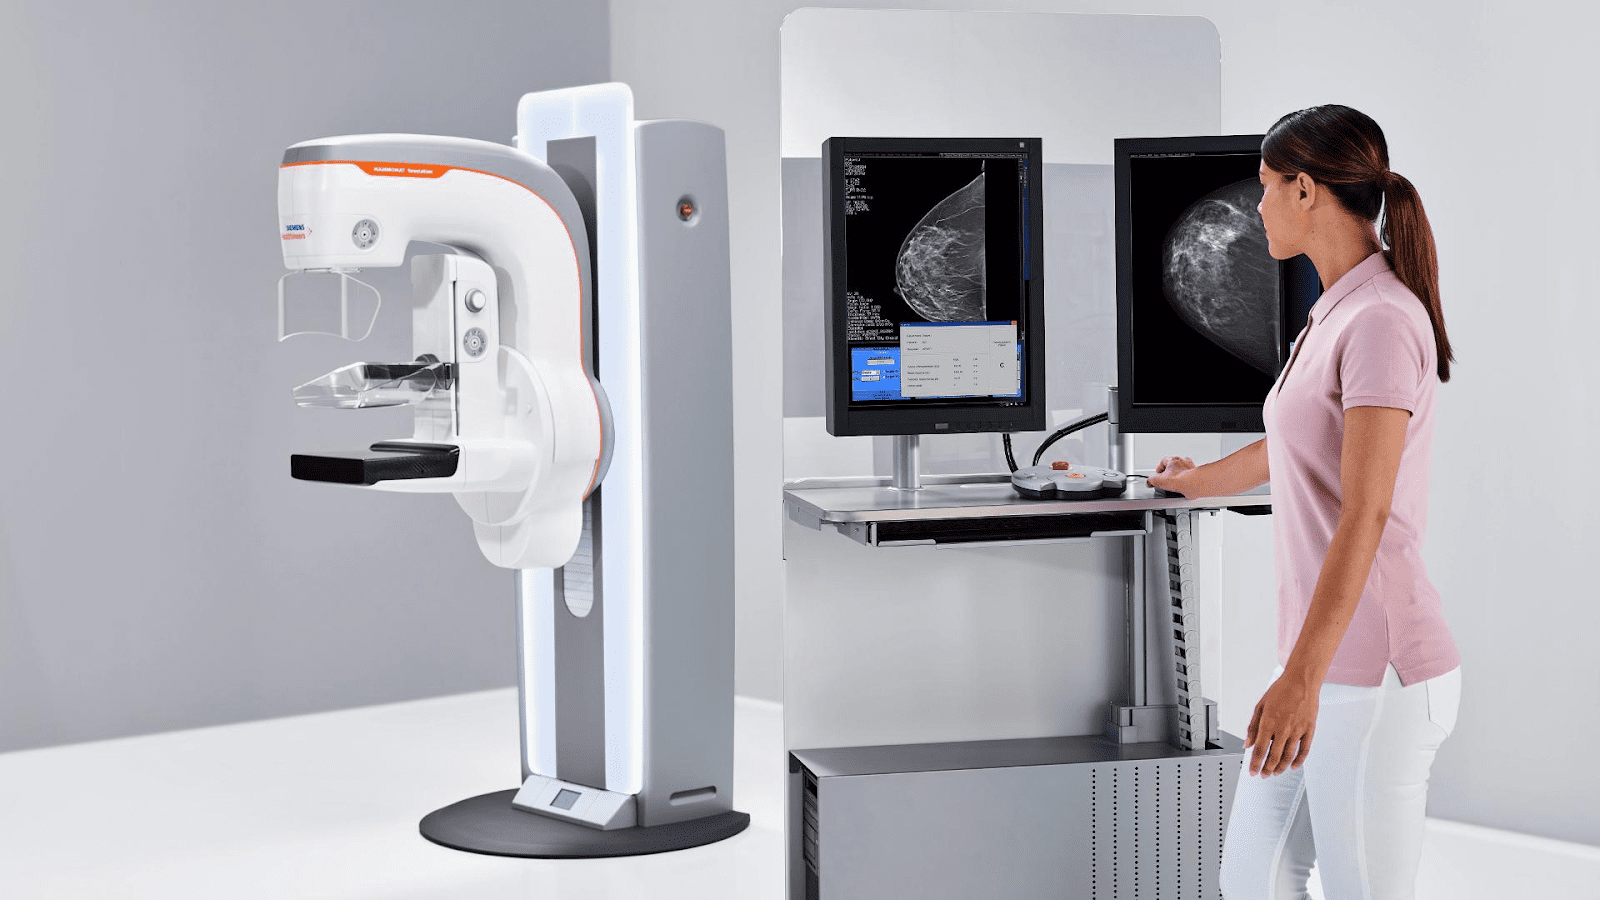

«AHS Breast Cancer Screening Program» – это провинциальная служба скрининга, которая работает над тем, чтобы увеличить количество женщин в возрасте от 45 до 74 лет, проходящих регулярную маммографию и другие обследования груди.

Это часть программы скрининга рака молочной железы Альберты, которая предлагает маммографию и информацию о здоровье груди женщинам в Эдмонтоне и в 120 общинах Альберты. Это очень интересный проект, ведь у службы есть 2 мобильные маммографические клиники на колесах, которые укомплектованы необходимым оборудованием для удобной диагностики.

“Insight Medical Imaging” предоставляет полный спектр услуг диагностики различных заболеваний груди, включая ультразвуковое исследование, ядерную медицину, МРТ и биопсию. Все услуги, предоставляемые клиникой, полностью аккредитованы Канадской ассоциацией радиологии и Обществом радиологов Альберты.

Клиника работает пять дней в неделю (с понедельника по пятницу). Во всех заведениях скрининга молочной железы работают настоящие профессионалы. Если после обследования вам рекомендуют дополнительные обследования или анализы, можно быстро сделать их в тот же день без необходимости согласования повторного обследования. Это уменьшает дополнительный стресс для пациентов и позволяет ускорить лечение. В клинике все сделано для того, чтобы обследование и лечение были комфортными. Здесь есть отдельная зона ожидания с удобными сиденьями, баром и напитками. Персонал клиники очень вежлив и готов всегда помочь.

Пройти маммографию можно также в центре «Medical Imaging». Это самый большой радиологический центр Альберты. Здесь работает более 100 радиологов с разными специализациями, а также более 450 технологов и вспомогательного персонала. Центр работает с 1996 года.

Процесс маммографии в центре проходит очень комфортно. Когда вы придете на приём, вас попросят переодеться в халат. Чтобы получить четкое изображение, технолог разместит вашу грудь на компрессионную пластину, а аппарат постепенно сжимает грудь между двумя пластинами. Это может привести к небольшой дискомфорт, но это важно для четкого изображения. Если у вас очень чувствительная грудь, рекомендуется приходить по меньшей мере за неделю до менструации.